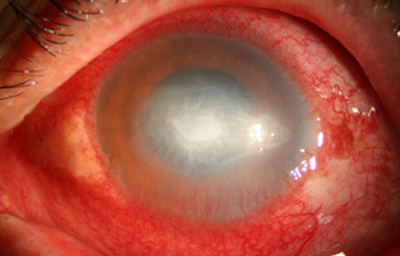

En su evolución se observará aumento del edema, agrandamiento y coalescencia de los infiltrados formando un anillo, (Figura 9, 10 y 11) que progresa hacia la formación de un absceso (Figura 12, 13 y 14), queratolisis superficial, adelgazamiento y perforación corneal (Figura 15 y 16).

Limbitis y escleritis anterior difusas.

La vascularización y el hipopion son poco frecuentes en los estadios tempranos de la queratitis. Con el tiempo, en los estados avanzados de invasión estromal, aparecen vasos estromales (Figura 17)